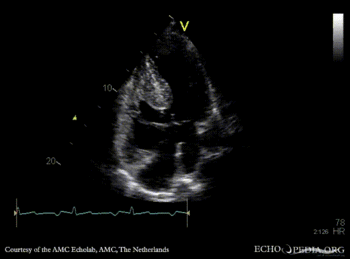

| A4CH: large AVSD